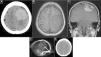

Las metástasis cerebrales son las lesiones intracraneales que se observan con mayor frecuencia en adultos. Por otra parte, los meningiomas son los tumores intracraneales primarios más frecuentes luego de los gliomas y son bien conocidas las características imagenológicas de estos, tanto en TAC como en RM. Sin embargo, hay lesiones que pueden simular meningiomas en estudios por imágenes, entre las que encontramos metástasis de tumores extracraneanos, afrontándonos a un reto diagnóstico y terapéutico. Presentamos el caso de una paciente con metástasis meníngea de un leiomiosarcoma uterino que no era conocido en el momento de la intervención quirúrgica.

Brain metastases are the most commonly seen intracranial lesions in adults. What is more, meningiomas are the most common primary intracranial tumours after gliomas and their imaging characteristics are well known in both CT and MRI scans. However, there are lesions that can mimic meningiomas in imaging studies, including metastases of extracranial tumours, confronting us with a diagnostic and therapeutic challenge. We present the case of a patient with meningeal metastasis of a uterine leiomyosarcoma that was not known at the time of the surgical intervention.